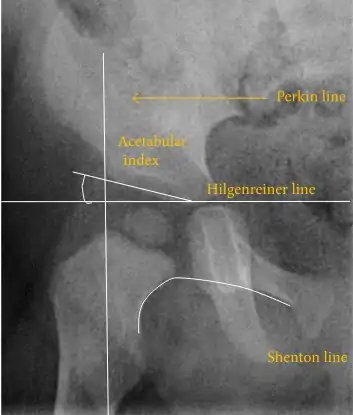

The most useful lines and angles that can be drawn in the pediatric pelvis assessing hip dysplasia are as follows:[43] Different measurements are used in adults.[43]